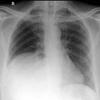

Pneumothorax

**tension pneumothorax** Small chest drain in situ Basal atelectasis left Surgical emphysema within mediastinum and soft tissue